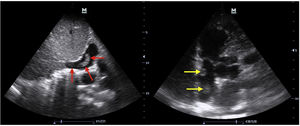

Ecocardiografía clínica a pie de cama. En la imagen de la izquierda se evidencia trombo en la vena cava inferior que incluso se extiende hasta la aurícula derecha como indican las flechas rojas, desde un plano subcostal en ventana subxifoidea. En la imagen de la derecha se visualizan dos trombos en tránsito en la aurícula derecha señalados con las flechas amarillas, desde un plano apical de dos cámaras en ventana apical.

Con la presentación clínica de disnea aguda en una paciente oncológica, llevamos a cabo una ecografía clínica de corazón, pulmonar y sistema venoso en miembros inferiores para descartar una causa pulmonar que justificara la disnea, la presencia de datos indirectos de tromboembolismo pulmonar en la ecocardiografía clínica o signos ecográficos de trombosis venosa profunda en el estudio venoso de ambos miembros inferiores. La ecografía pulmonar con sonda convexa fue normal con deslizamiento pleural presente y líneas A bilateral, sin derrame pleural en ambos hemitórax. El sistema venoso profundo y superficial de ambas piernas no mostró signos de trombosis con técnica de compresión simplificada con sonda lineal. Sin embargo, en el plano apical de dos cámaras con sonda sectorial en el ápex cardíaco se visualizaron dos trombos en tránsito en la aurícula derecha que se asociaron a un trombo que se introdujo en la aurícula derecha, presente en la porción más proximal de la vena cava inferior visualizado en un plano subcostal (fig. 1). Ya con el diagnóstico del trombo visualizado en la vena cava inferior se derivó a la paciente al servicio de urgencias hospitalario de referencia para establecer las medidas de soporte hemodinámico y terapéuticas correspondientes.